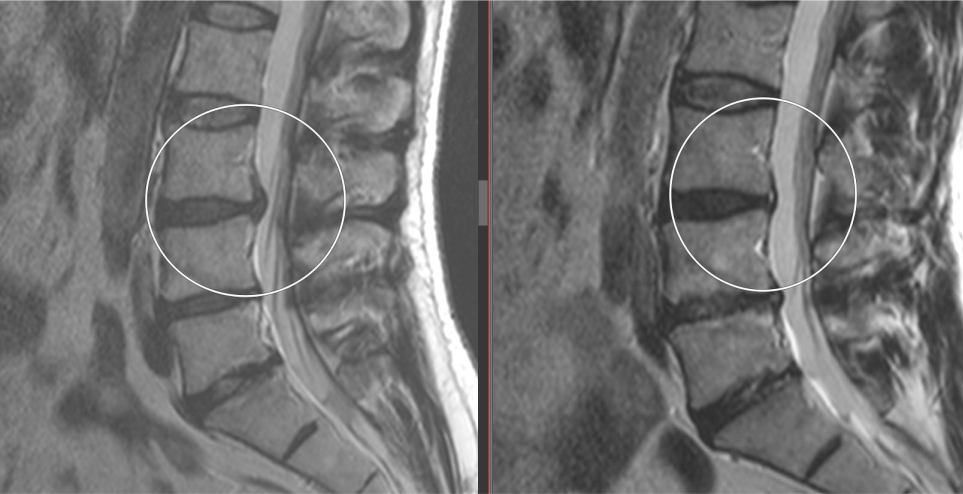

Латерализация грыжи